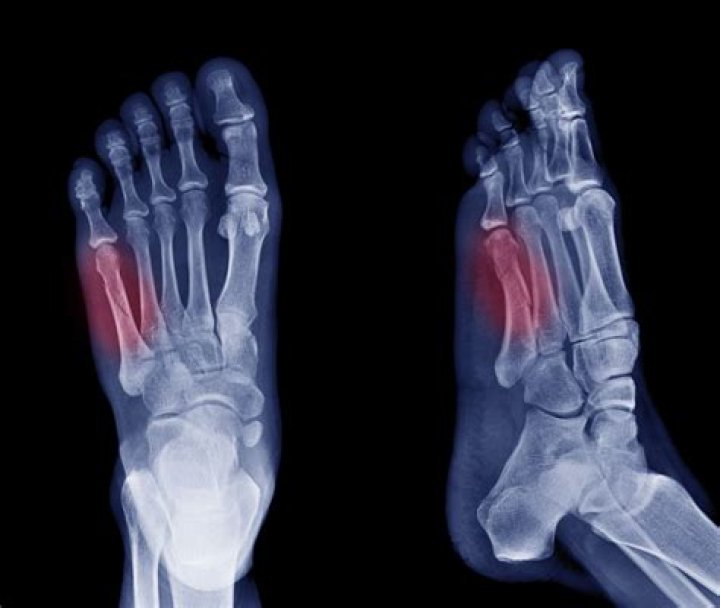

Can you walk on a fractured foot?

Pain in response to pressure is often the key for your doctor to diagnose a hairline fracture. MRI: The best imaging test for determining hairline fractures is an MRI. This test uses magnets and radio waves to provide images of your bones. An MRI will determine a fracture before an X-ray can.

Do fractures show up right away?

Stress fractures often can't be seen on regular X-rays taken shortly after your pain begins. It can take several weeks — and sometimes longer than a month — for evidence of stress fractures to show on X-rays. Bone scan.